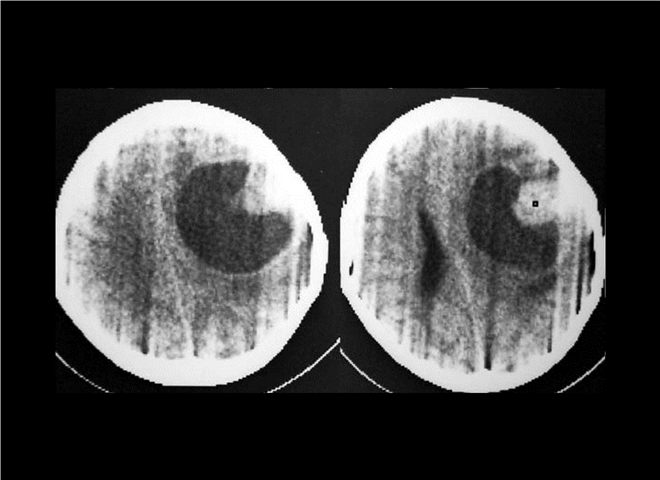

13_CT增强扫描